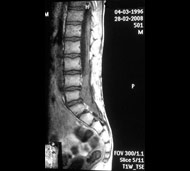

Спинальна магнітно-резонансна томографія (МРТ). Замість радіаційного випромінювання в МРТ використовуються потужні магнітні і радіохвилі для отримання зображення поперечного перерізу хребта. МРТ чітко відображає спинний мозок і нерви і забезпечує краще зображення пухлин кісток, ніж комп'ютерна томографія (КТ). Вам можуть ввести в вену кисті або передпліччя контрастну речовину, яка висвітлює деякі пухлини. Крім цього, використовують сканери з високою інтенсивністю сигналу для виявлення невеликих пухлин, які можна не помітити.